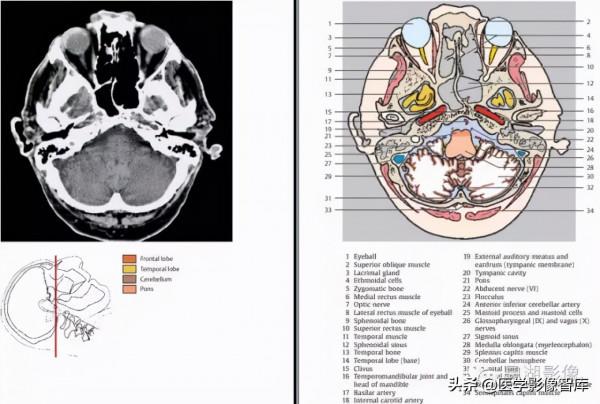

1.額骨 2.額竇 3.上斜肌 4.眼球 5.眼靜脈 6.上直肌 7.直回合嗅球 8.眶後脂肪 9.顳肌 10.視神經 11.蝶竇 12.蝶骨 13.顳下回 14.眶上組織 15.三叉神經 16.頸內動脈 17.橋腦池 18.海綿竇 19.乳突竇 20.基底動脈 21.橋腦 22.腦橋小腦池 23.小腦腳中下部 24.面、前庭蝸神經(內耳道)25.乙狀竇 26.乳突和乳突細胞 27.小腦蚓 28.第四腦室 29.枕竇 30.小腦半球 31.枕骨32.頭半棘肌

1.眼球 2.上斜肌 3.淚腺 4.篩骨竇 5.顴骨 6.內直肌 7.視神經 8.外直肌 9.蝶骨 10.上直肌 11.顳肌 12.蝶竇13.顳骨 14.顳葉(底部)15.斜坡(由顱骨的枕大孔向上至背鞍)16.顳下頜關節和下頜頭17.基底動脈18.頸內動脈19.外耳道(骨膜)20.鼓室 21.橋腦 22. 外展神經 23.絨球 24.小腦下前動脈 25.乳突和乳突細胞 26.舌咽神經和迷走神經 27.乙狀竇 28.延髓 29.頭夾肌 30.小腦半球 31.枕骨 32.枕竇 33.頭後小直肌 34.頭半棘肌